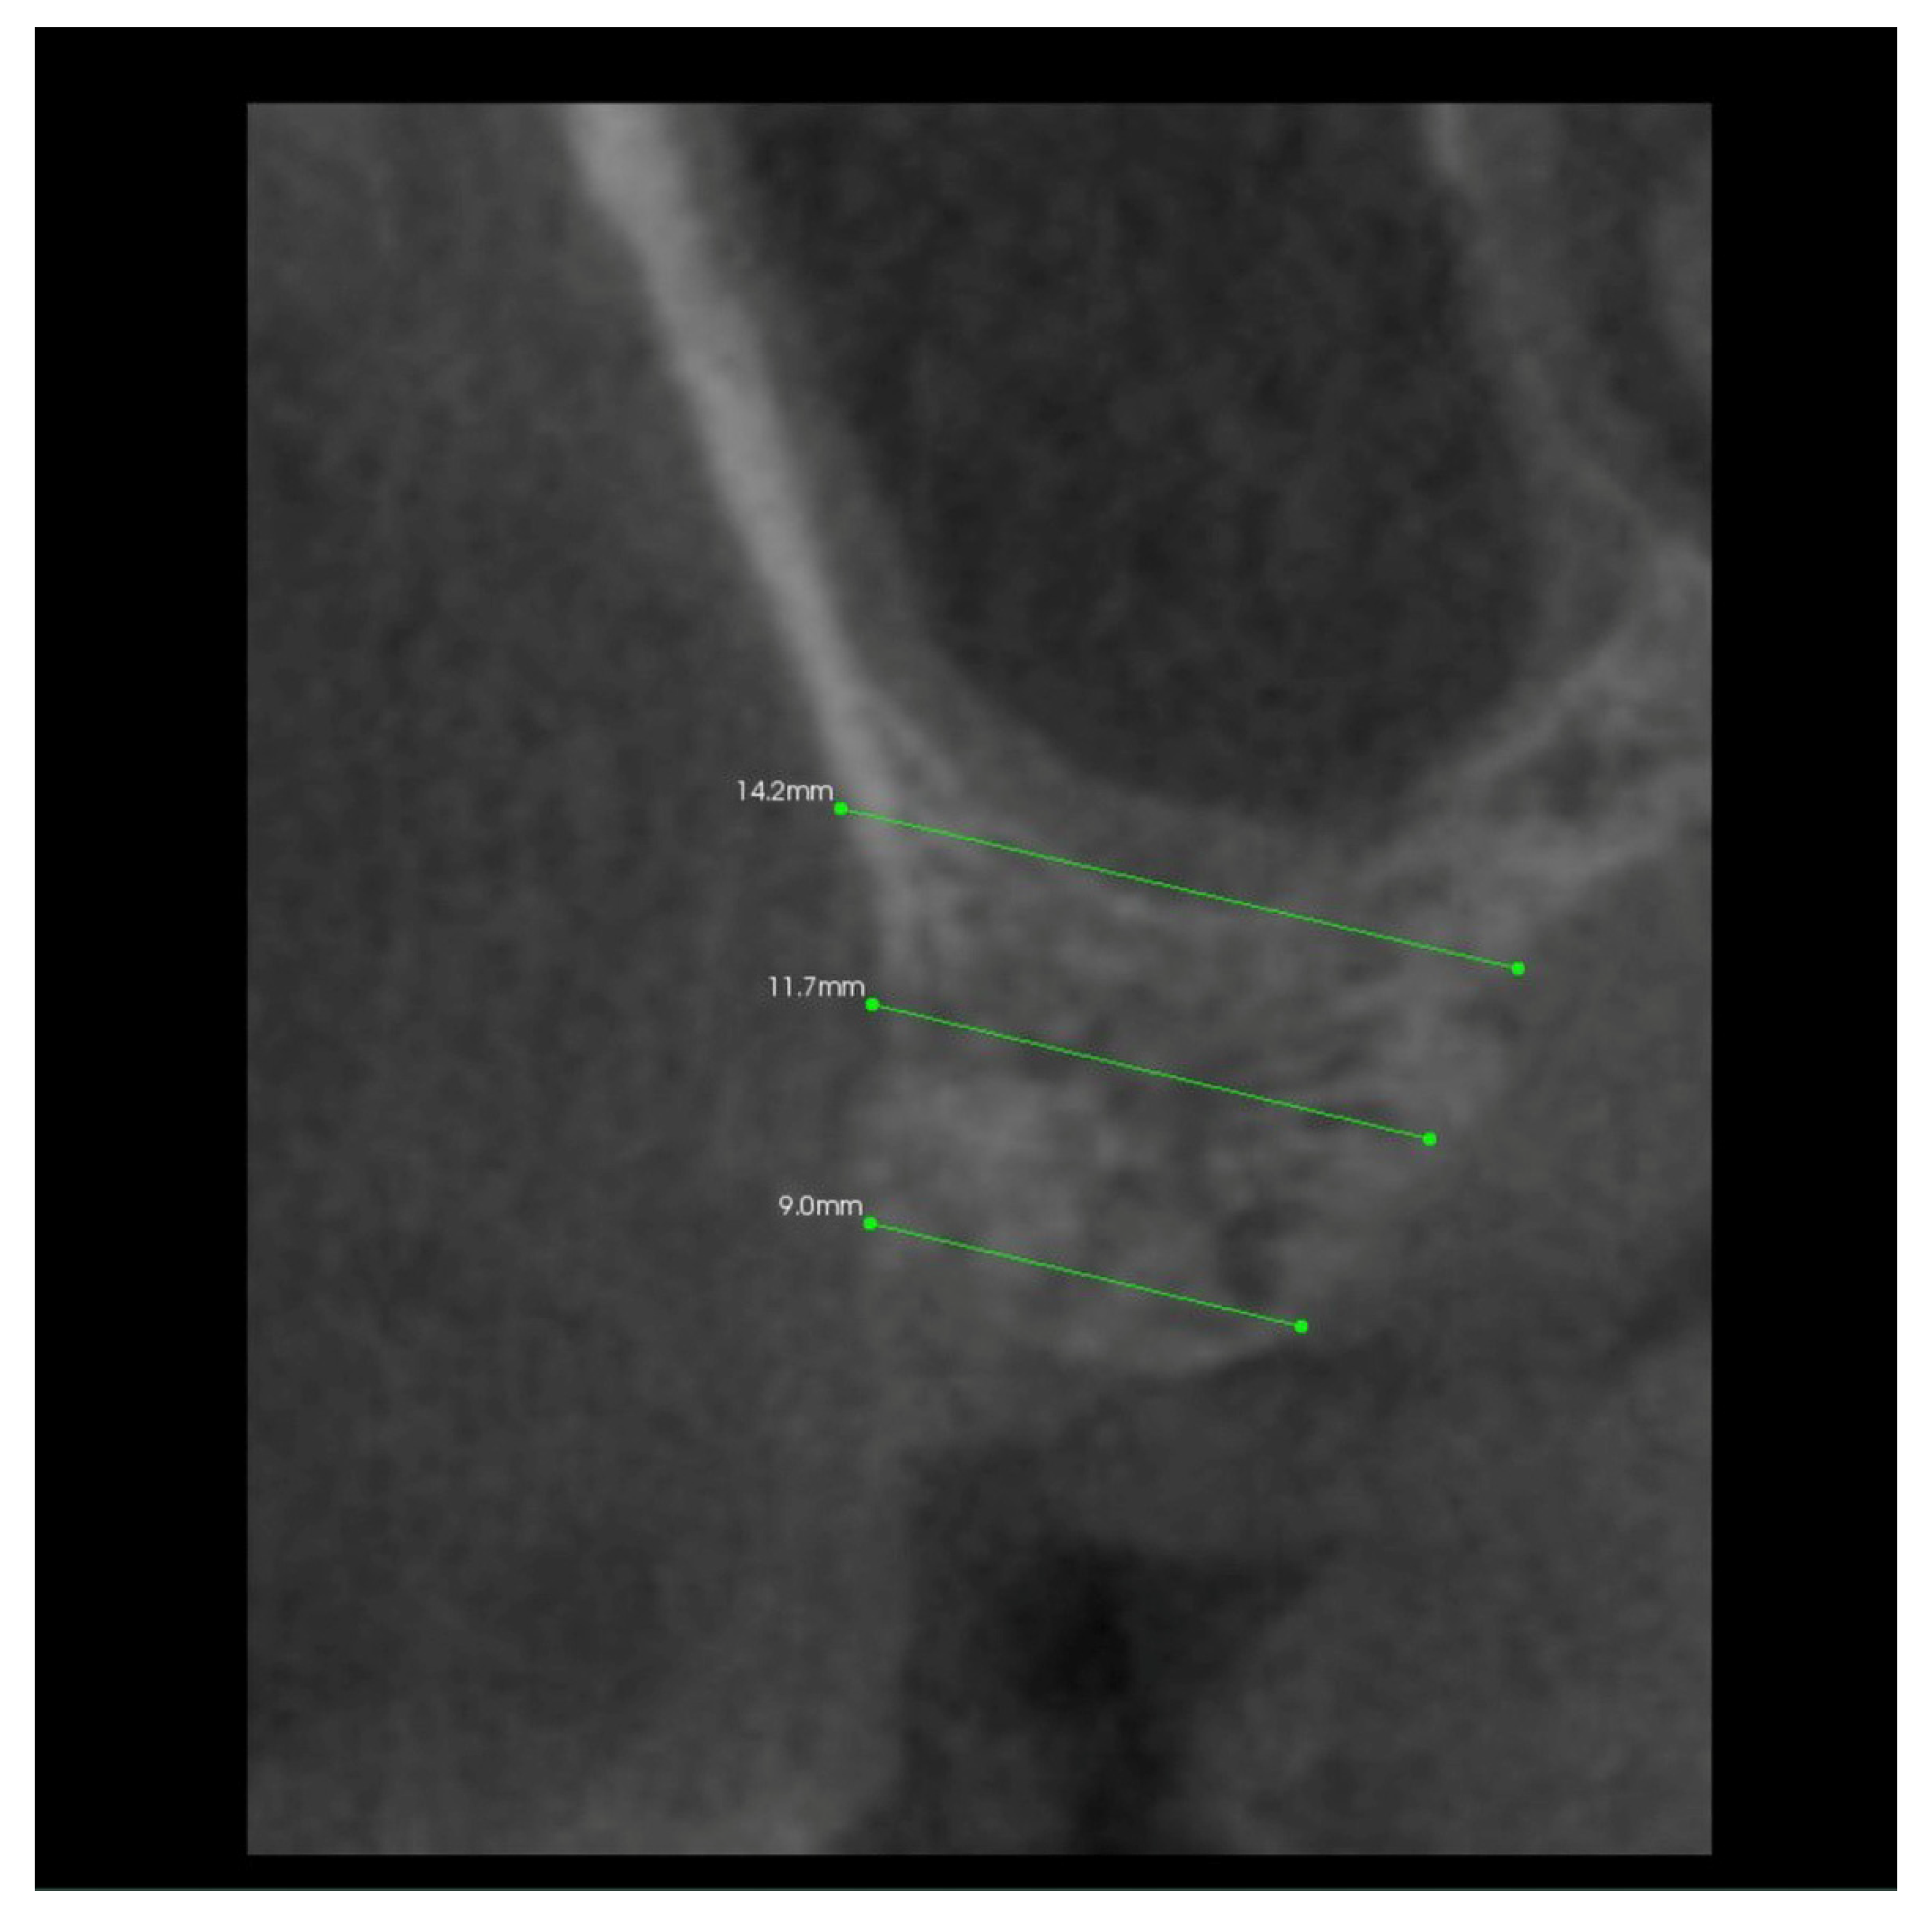

- The A line drawn through the apexes of the teeth adjacent to the post-extraction socket;

- The IC line drawn through the top of the buccal cusps of the teeth adjacent to the pos-extraction socket;

- The midline of the post-extraction socket (alveolus).

- Point (A)

- 1/3 of the distance between the A line and the IC line following the midline;

- Point (B)

- At the intersection of the midline and the A line.

3.2. The Results of Mean Values of the Alveolar Process Width and Height Measurements Performed after Tooth Extraction within the Space of 6 Months for Two Different Alveoli in the Same Patient

3.4. The Results of Mean Measurements of Height and Width of the Alveolar Processes of Two Extraction Sites (with and without PRF) in the Same Patient after 6 Months from Tooth Extraction Based on the Analysis of Volumetric Tomography